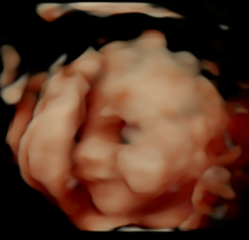

We need to save up for my last embryo to be put back, and so we just carried on trying naturally in the meantime. I then got a positive pregnancy test in July and I thought it was going to end in another loss, I was more or less expecting it at this point. However, it turns out it was the best £4k we've spent, because for the very first time ever, I got this on Wednesday! I still can't believe it!

(I was 12+3 by last menstrual period, the sonographer measured 12+1 in the scan, so I'm 12+4 today)